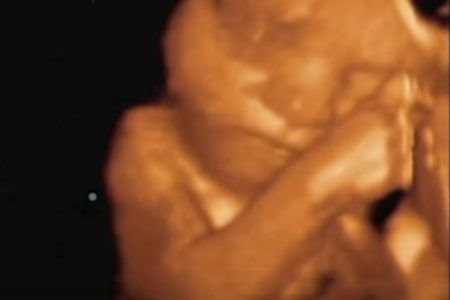

Na snimku se može videti njena bebica koje se pomera, trlja okice i mazi se o mamin stomak.

Ovo je neverovatan prikaz majčine utrobe novom metodom 4D snimka, koji postaje sve popularniji u svetu.